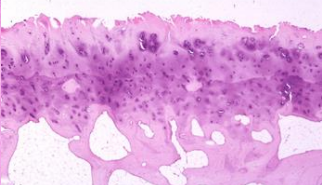

What is the basic, non-mineralized matrix that is first laid down in bone? What does this substance look like on an H&E stain?

Osteoid. It stains pink.

What is your diagnosis?

Osteoporosis. Note lack of trabecullar interconnections, thin trabeculae, quiescent cellular activity, and thin cortex.